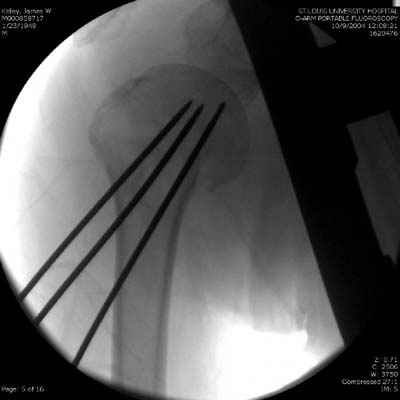

Женя, а как ты водишь спицы, в смысле, как делаешь входное отверстие, и как в него проводишь V-спицу? А то о дна из спиц, та, у которой не дошла до головки одна палочка буквы V, как-то выглядит на рентгенограмме, как будто или через очень большое отверстие введена, или каждая половинка через отдельные отверстия.

Мне кажется, проблема в том, что не все концы спиц зашли в головку, и зашедшие - недостаточно далеко прошли.

Спицы провожу по передней и задней поверхностям плечевой кости через 4,5 мм отверстия на разных уровнях.

Уточни - обе части буквы V вводишь в одно отверстие? А то по снимкам выглядит, что в разные.

V-спица проводится через 4,5 мм отверстие. Видимо, из-за разной длины вторая половина спицы *пролетела* мимо отверстия, что и привело к вторичному смещению костных фрагментов.

Здравствуй Женя. Во первых спицы, вводимые в головку плеча ретроградно, никогда не имели V-образную форму, если говорить о методике моей операции ЦИТО. Чтобы легче было запомнить Y-образную форму, вспомни крепление новогодних елочных шаров - очень демонстративно. Кроме того если ты внимательно посмотришь, то увидишь, что вся конструкция имеет некоторую кривизну по плокскости, величину, которой ты можешь задать сам. Сначала мы проводим проксимальный пучок, а в момент пересечения линии перелома мы

ротируем спицу таким образом, чтобы дистальный изгиб прямо противодействовал смещающим силам - поврот за ушко под контролем ЭОПа. Дистальный пучок стараемся провести так, чтобы его бранши расклинились и прошли по обе стороны предыдущего пучка, что создает дополнительное напряжение на

протяжении контакта. Для оценки правильности проведения спиц очень важно, чтобы ЭОП стоял строго перпендикулярно плоскости сустава, в противном случае - в рентгене есть эффект отбрасывания тени - прохождение косого луча дает удлиненное изображение спиыц и создается впечатление, что спица стоит уже в субхондральном слое. На первых операциях у нас было довольно частое несовпадение длины контрольной спицы и мы провизорно добавляли от 0,5 до 1,0 см уже на фиксирующем пучке. Входные отверстия лучше располагать по наружной и передней поверхности плеча на расстоянии не менее 2-х диаметров головки.

Такой выбор входных отверстий обусловлен прямой возможностью попадания в малый и большой бугорки за счет изгиба спиц по длине и отражения из от внутреннего кортикала проксимальнее точки введения. Поскольку анатомически бугорки не составляют артикулирующую поверхность, то некоторое выстояние спиц только усилит стабильность. Входное отверстие мы используем 6 мм в диаметре, для эффективного раскрытия петли-пружины. Спицы перед проведением

проверяем на достаточную эластичность и упругоустойчивость, мягкие спицы отбраковываем. В данном примере создалось впечатление, что одна бранша V-спицы скользнула по картикалу снаружи? Все это безболезненно можно переделать, расширив теже отверстия, изогнув спицы, повернув их в разные стороны и добавив еще пучки Y-ОБРАЗНЫХ, а не V-образных (эти пучки выталкивает, особенно если они прямые - пружина работает в обе стороны).